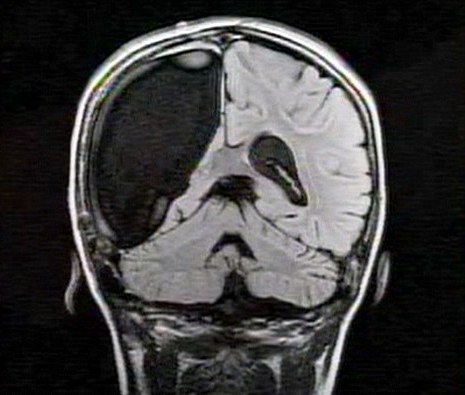

卡梅倫莫特在3歲那年患上一種被稱(chēng)作大腦功能紊亂“拉斯穆森”綜合癥,這種病癥誘發(fā)患者的無(wú)序暴力行為和嚴(yán)重的癲癇。醫(yī)生建議,治療這種病癥只能通過(guò)嘗試消除引發(fā)此癥狀的大腦組織。而手術(shù)讓莫特失去了幾乎整個(gè)半邊的大腦。

據(jù)悉,莫特在手術(shù)后已經(jīng)可以跑動(dòng)和玩耍,她在術(shù)后的第四周離開(kāi)了醫(yī)院。醫(yī)生表示,雖然右半邊大腦的切除可能會(huì)給莫特帶來(lái)半身不遂的風(fēng)險(xiǎn),但孩子剩余的大腦仍具有很強(qiáng)的重組和布線(xiàn)能力。